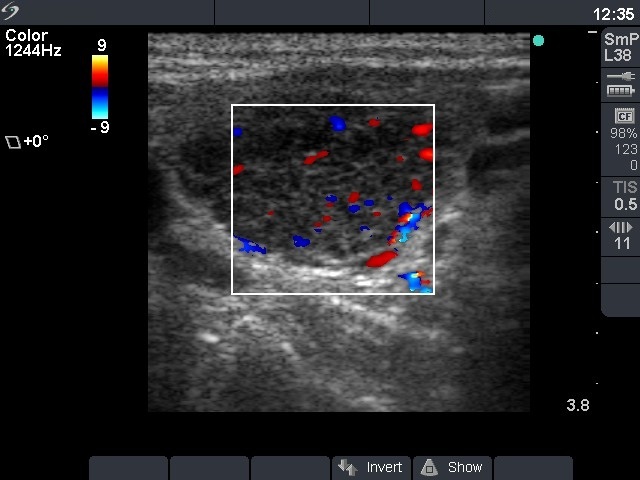

Chronic lymphocytic thyroiditis - Case 50. (ultrasonographic picture 4)

Left lobe, longitudinal scan, color Doppler mode. Type 3 vascular pattern.